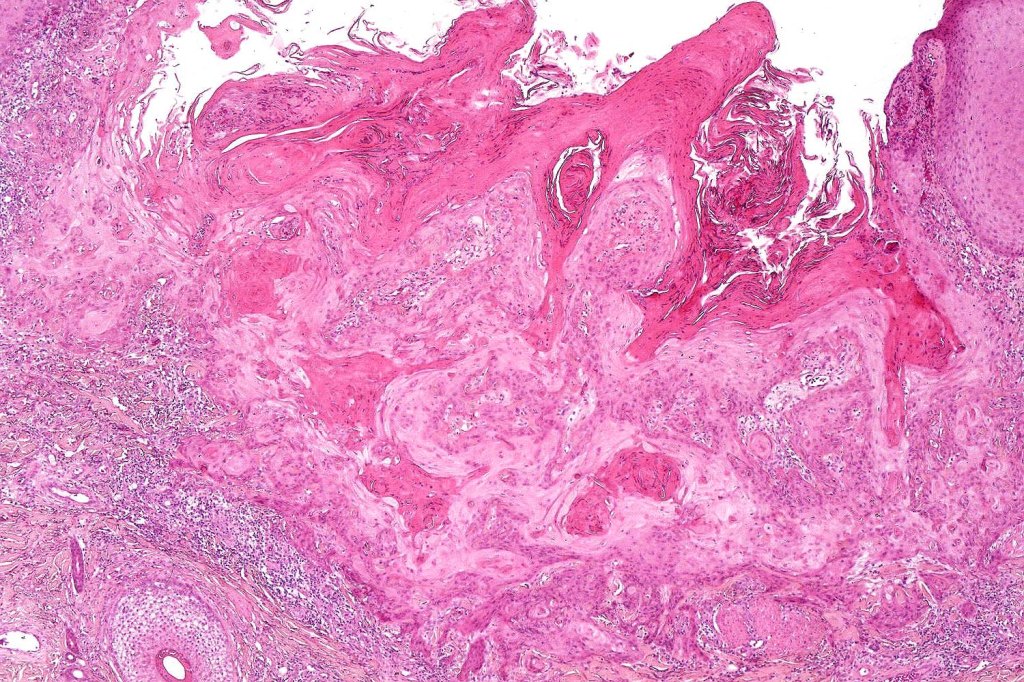

•Keratoacathoma (nowdays regarded as a variant of well differentiated squamous carcinoma) is characterized by a crateriform squamous epithelial lesion (dilated follicular infundibulum) with central keratin plug and adjacent collarette extending to the mid-dermis

•Well differentiated squamous epithelium often with a characteristic ground-glass appearance

•Only mild pleomorphism & basally located mitoses

•Neutrophil-rich microabscesses & necrosis

Below is a fascinating case shared on McKee Derm by Dr. James Simpson. There is an obvious keratoacanthoma but at the edge of the lesion there is marked atypia with nuclear enlargement and pleomorphism. This is also evident in the adjacent epidermis and in the deeper nests.